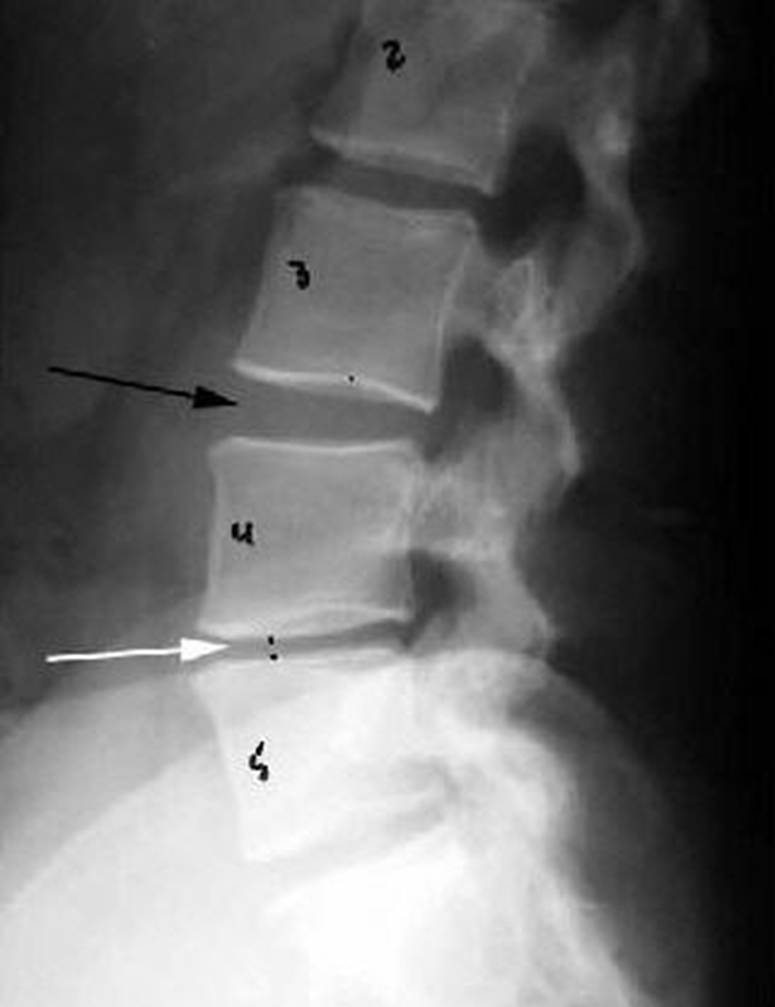

Osteochondroma

(Exostosis)

Benign projection of bone with a cartilaginous cap

Cause: idiopathic, hereditary

Complications: may turn malignant, pain, fracture of stalk

Radiographic Appearance: long axis of bone growth runs parallel to the parent bone and points away from nearest joint

Technical: No manual exposure factor change

Prognosis: Good, surgery only needed when there are mechanical

impingements